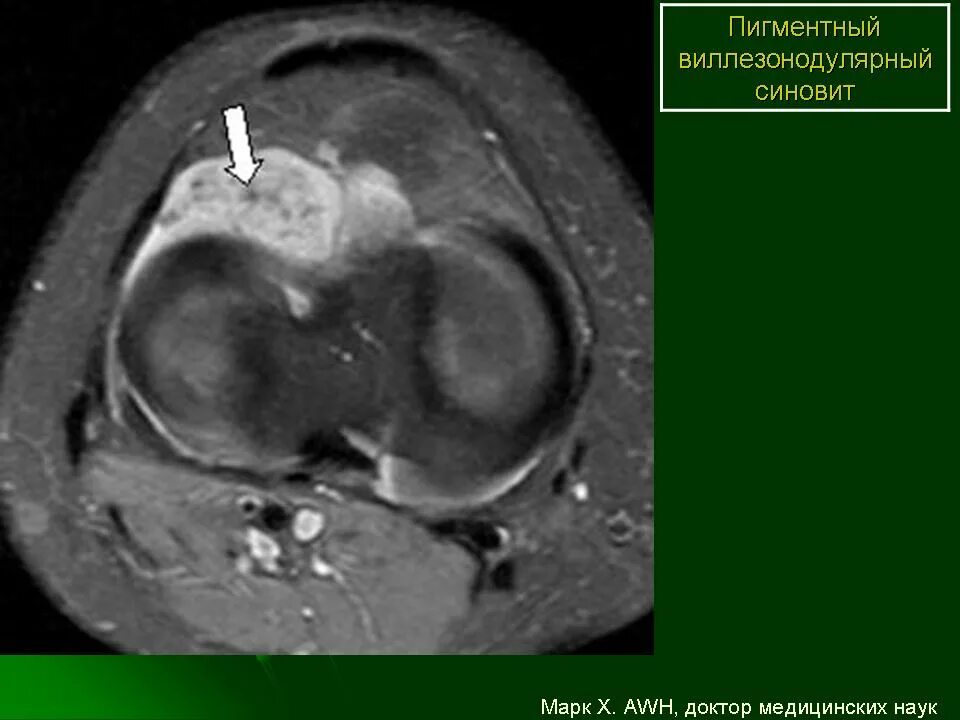

Пигментный виллонодулярный синовит